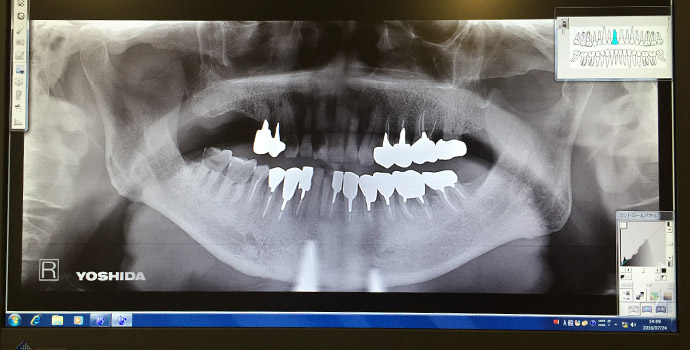

デジタルレントゲン

当院ではあえてCTを採用せず、デジタルパノラマ・セファロレントゲンを採用しました。

CTの1回あたりの撮影の際の被爆量は250μSであるのに対し、デジタルパノラマ・セファロレントゲンは10分の1の25μSvであるからです。

(デジタルパノラマ・デンタルレントゲンは10μS)

被爆量の低減について、医療側の努力が必要であるからです。

3次元的なレントゲンの検査方法として、下記の様な物があります。

方向の異なる画像を読影して診断する事が可能です。